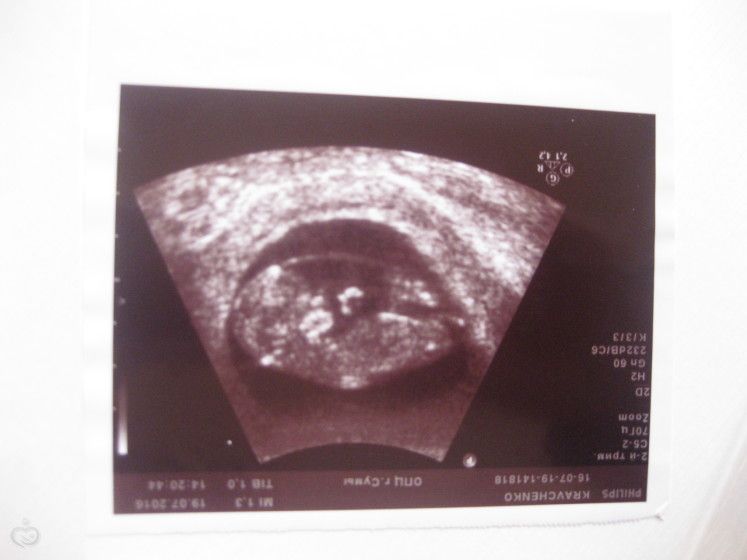

Узи в 12 недель как вам кажется кто у нас живет? Просто ради интереса, понятное дело, что только узи точно скажет, но все-таки интересно)